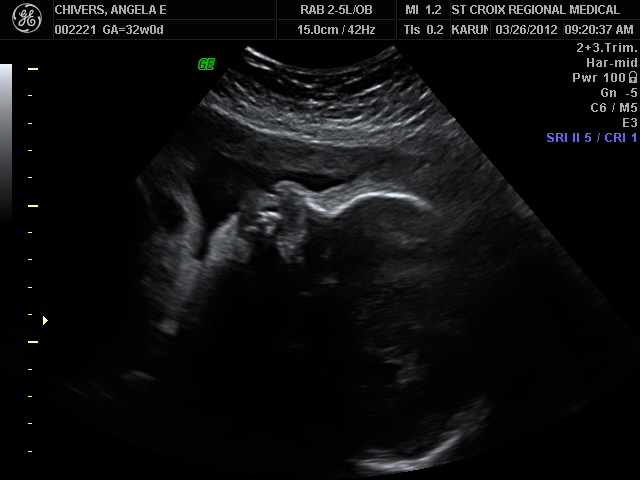

At 32 weeks we started having weekly biophysical profiles. It is very reassuring to see him alive and well on the screen every week, and to hear his strong beating heart. Weight estimate at 32 weeks was 4 # 6 oz.